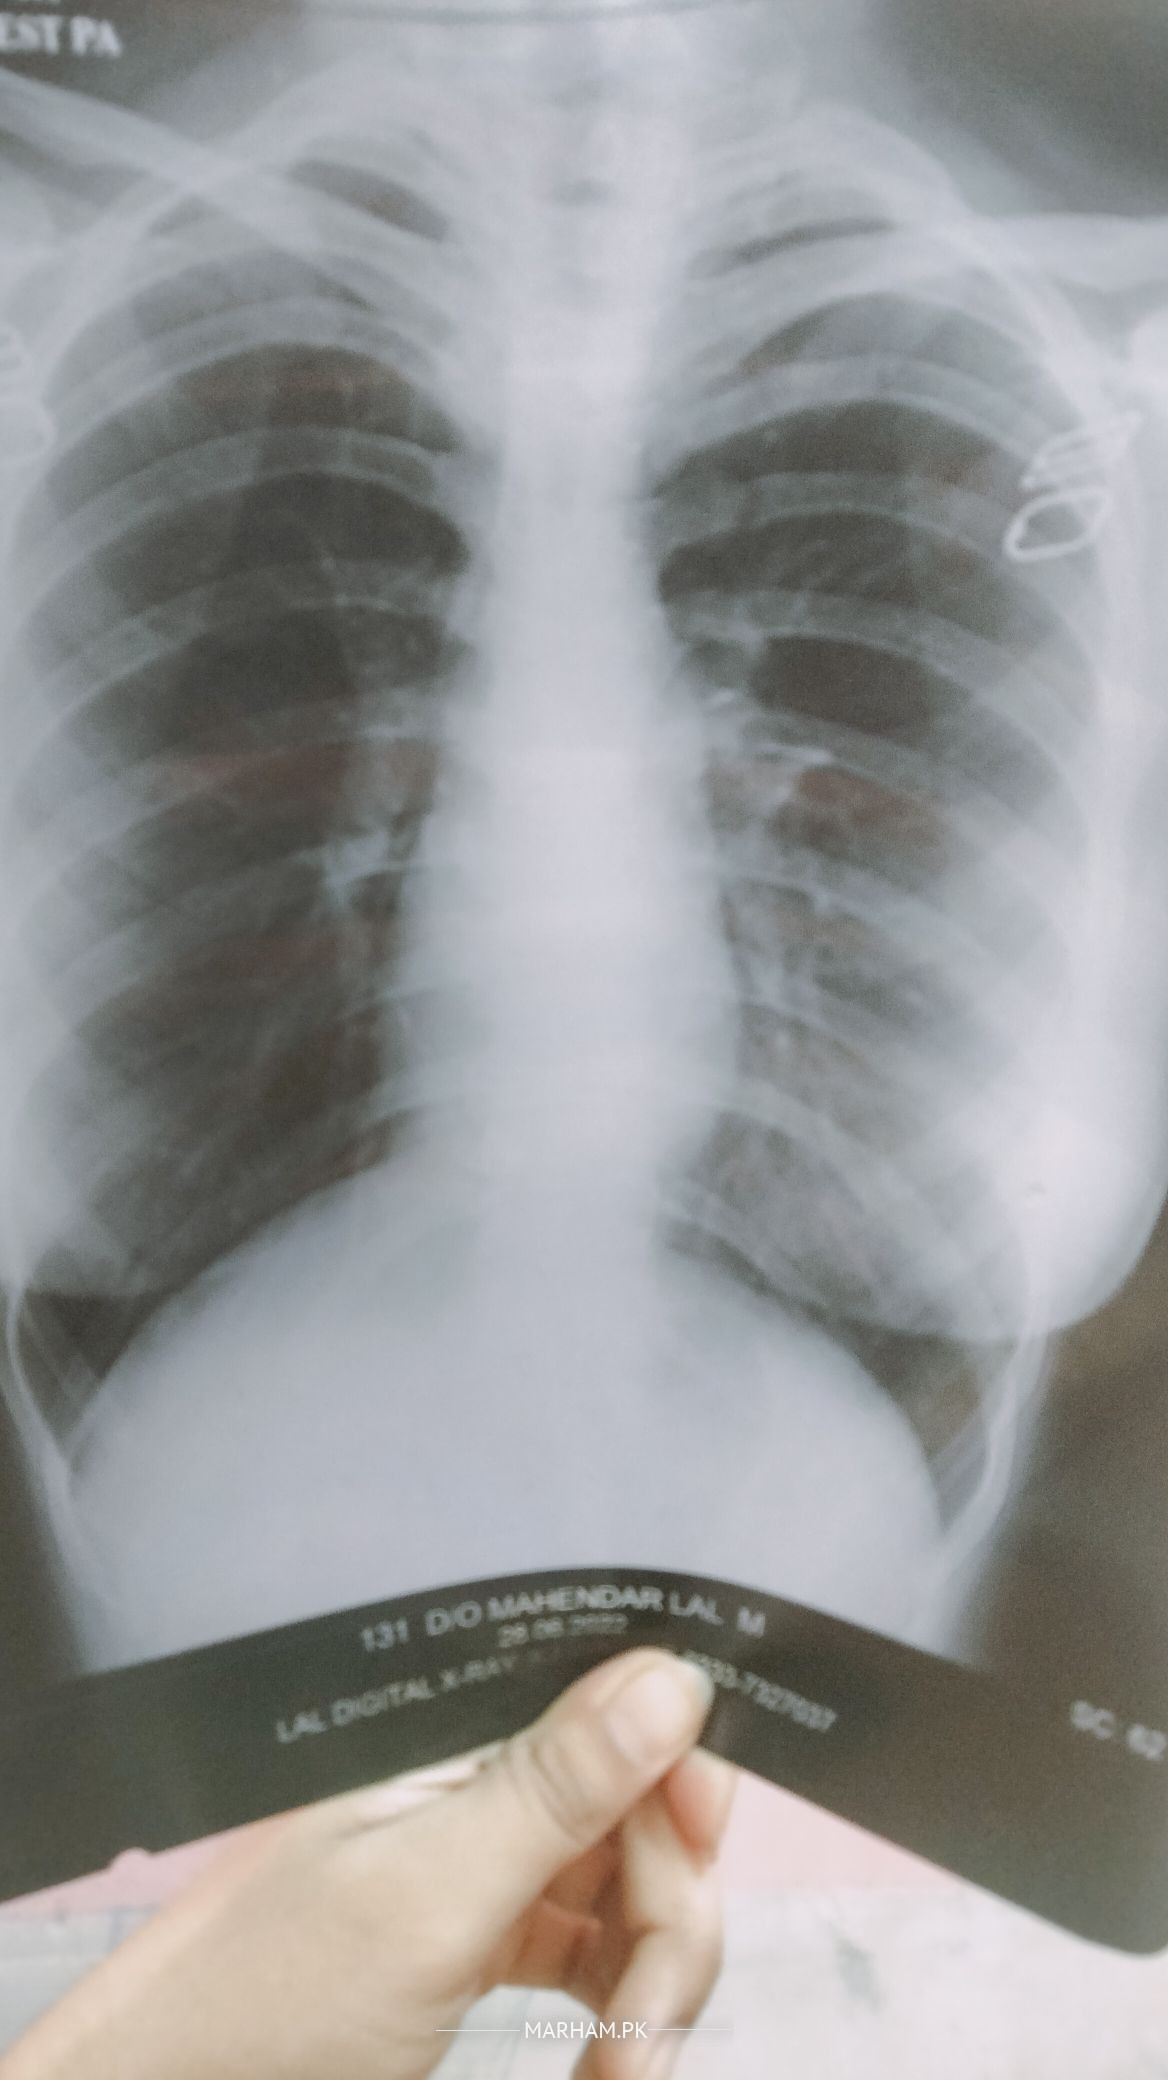

need diagnosis for this chest saud its infection i want to know the detail

there are signs of infection

Seems to infection signs

Please share your complain then we decide for further plan of treatment, Xray seems to be ok but patient check is important to rule out other cause.

In your there is some haziness on the left lower chest but no convincing sign of infection.

Proper history with supportive blood tests are required.

them what is the reason of cough...i took allergic medicine too but nothing works. i have breathlessness too when climbing stairs sometimes during talking fast.. right now i dont have cough kyuk medicine le rh hun but the dose of Medicine is over tomorrow and i fear the cough will come again